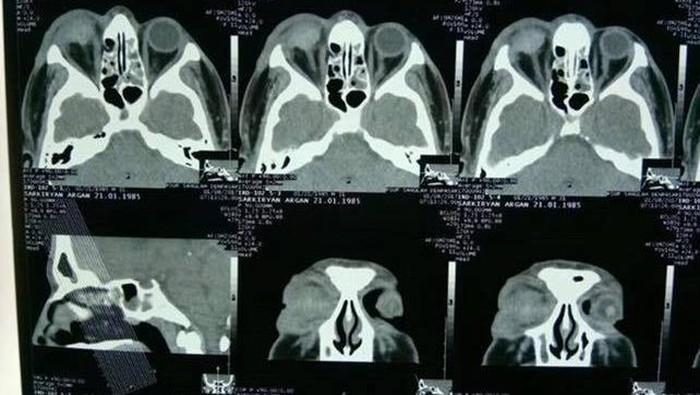

Ia kemudian dilarikan ke RS BIMC, Jl By Pass Ngurah Rai, Kuta, Bali. Dennis menjelaskan dokter menyatakan mata sebelah kanan temannya tak bisa diselamatkan, sehingga mengalami kebutaan permanen.